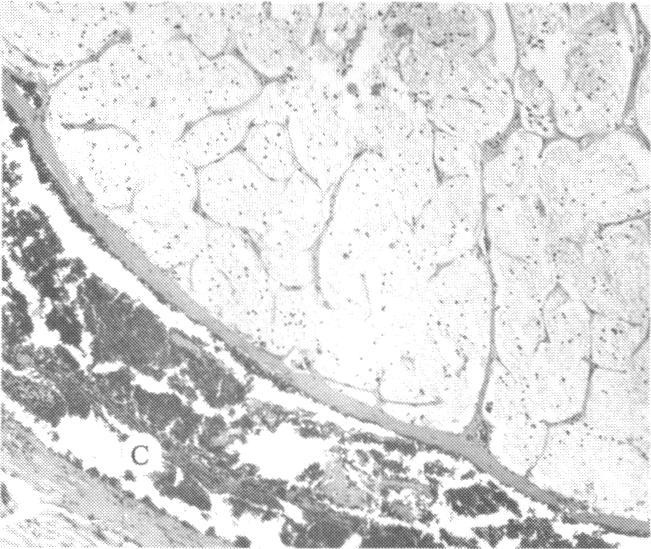

The clinical and histopathologic features of 29 eyes from 29 patients with central retinal vein occlusion (CRVO) are reported. A fresh or a recanalized thrombus was observed in each eye. This study considers the temporal aspects of the cases, and it notes the different morphologic features of the occlusion. These observations explain most of the variability of the changes observed in previous reports. We believe that these different features represent the various stages in the natural evolution of such a thrombus. The interval between CRVO and histopathologic study in our series ranged from six hours to more than 10 years. Local and systemic factors were reviewed and were found to be important in the pathogenesis of thrombus formation. Local diseases with a predisposing effect on CRVO included: glaucoma, papilledema, subdural hemorrhage, optic nerve hemorrhage, and drusen of the optic nerve head. Associated systemic diseases included: hypertension, cardiovascular and cerebrovascular disease, diabetes mellitus, and leukemia with thrombocytopenia. A fresh thrombus in the CRVO was observed in three (10.3%), and a recanalized thrombus in 26 eyes (89.7%). Endothelial-cell proliferation was a conspicuous feature in 14 (48.3%) of the eyes. Chronic inflammation in the area of the thrombus, and/or vein wall or perivenular area was observed in 14 (48.3%) of the eyes. Arterial occlusive disease was observed in seven eyes (24.6%). Cystoid macular edema was found in 26 (89.7%) of the eyes.

报告了29例视网膜中央静脉阻塞(CRVO)患者29只眼的临床和组织病理学特征。每只眼中均观察到新鲜或再通的血栓。本研究考虑了病例的时间因素,并记录了阻塞的不同形态学特征。这些观察结果解释了先前报告中观察到的变化的大部分变异性。我们认为这些不同特征代表了此类血栓自然演变的各个阶段。我们系列中CRVO与组织病理学研究之间的间隔时间从6小时到10多年不等。对局部和全身因素进行了回顾,发现它们在血栓形成的发病机制中很重要。对CRVO有 predisposing 作用的局部疾病包括:青光眼、视乳头水肿、硬膜下出血、视神经出血和视神经乳头玻璃膜疣。相关的全身疾病包括:高血压、心血管和脑血管疾病、糖尿病以及伴有血小板减少的白血病。在CRVO中观察到3只眼(10.3%)有新鲜血栓,26只眼(89.7%)有再通血栓。14只眼(48.3%)中内皮细胞增殖是一个显著特征。14只眼(48.3%)中观察到血栓区域、和/或静脉壁或静脉周围区域有慢性炎症。7只眼(24.6%)中观察到动脉闭塞性疾病。26只眼(89.7%)中发现黄斑囊样水肿。 (注:文中“predisposing”可能是“易患的”意思,但在专业医学语境中,可能有更准确特定含义,这里按常见理解翻译,具体含义需结合医学专业知识进一步确认。)